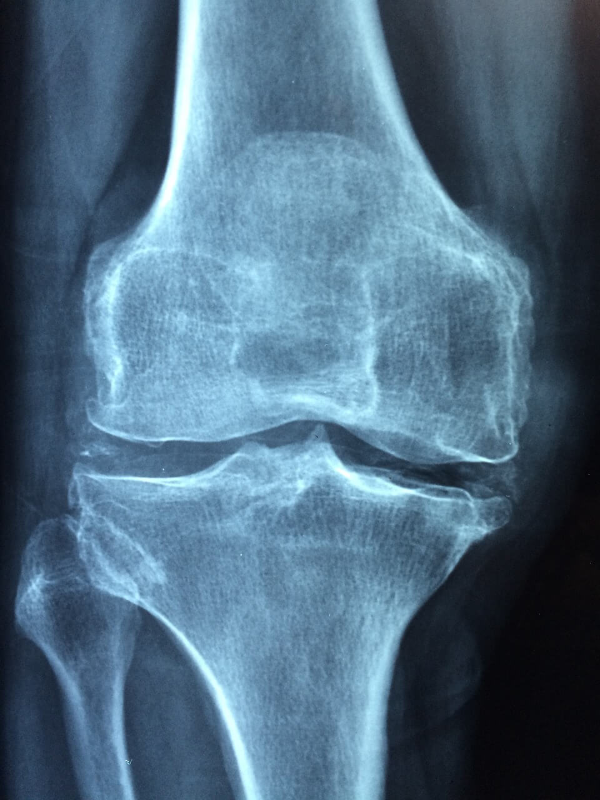

6. 통증이 잦다면 전문가 상담도 필수

생활습관을 바꿨는데도 통증이 계속되거나 점점 심해진다면, 반드시 병원을 찾아 정밀 검사를 받아야 합니다. 특히 관절염이나 류머티즘성 질환은 초기에는 단순한 통증처럼 느껴지기 때문에 자가진단은 위험할 수 있어요. 진료를 통해 정확한 원인을 파악하고, 필요한 치료를 시작하는 것이 관절 건강을 지키는 지름길입니다.

- 관절 MRI/X-ray 검사

- 관절염, 류머티즘, 연골 손상 진단

- 맞춤형 물리치료 및 약물 처방 가능